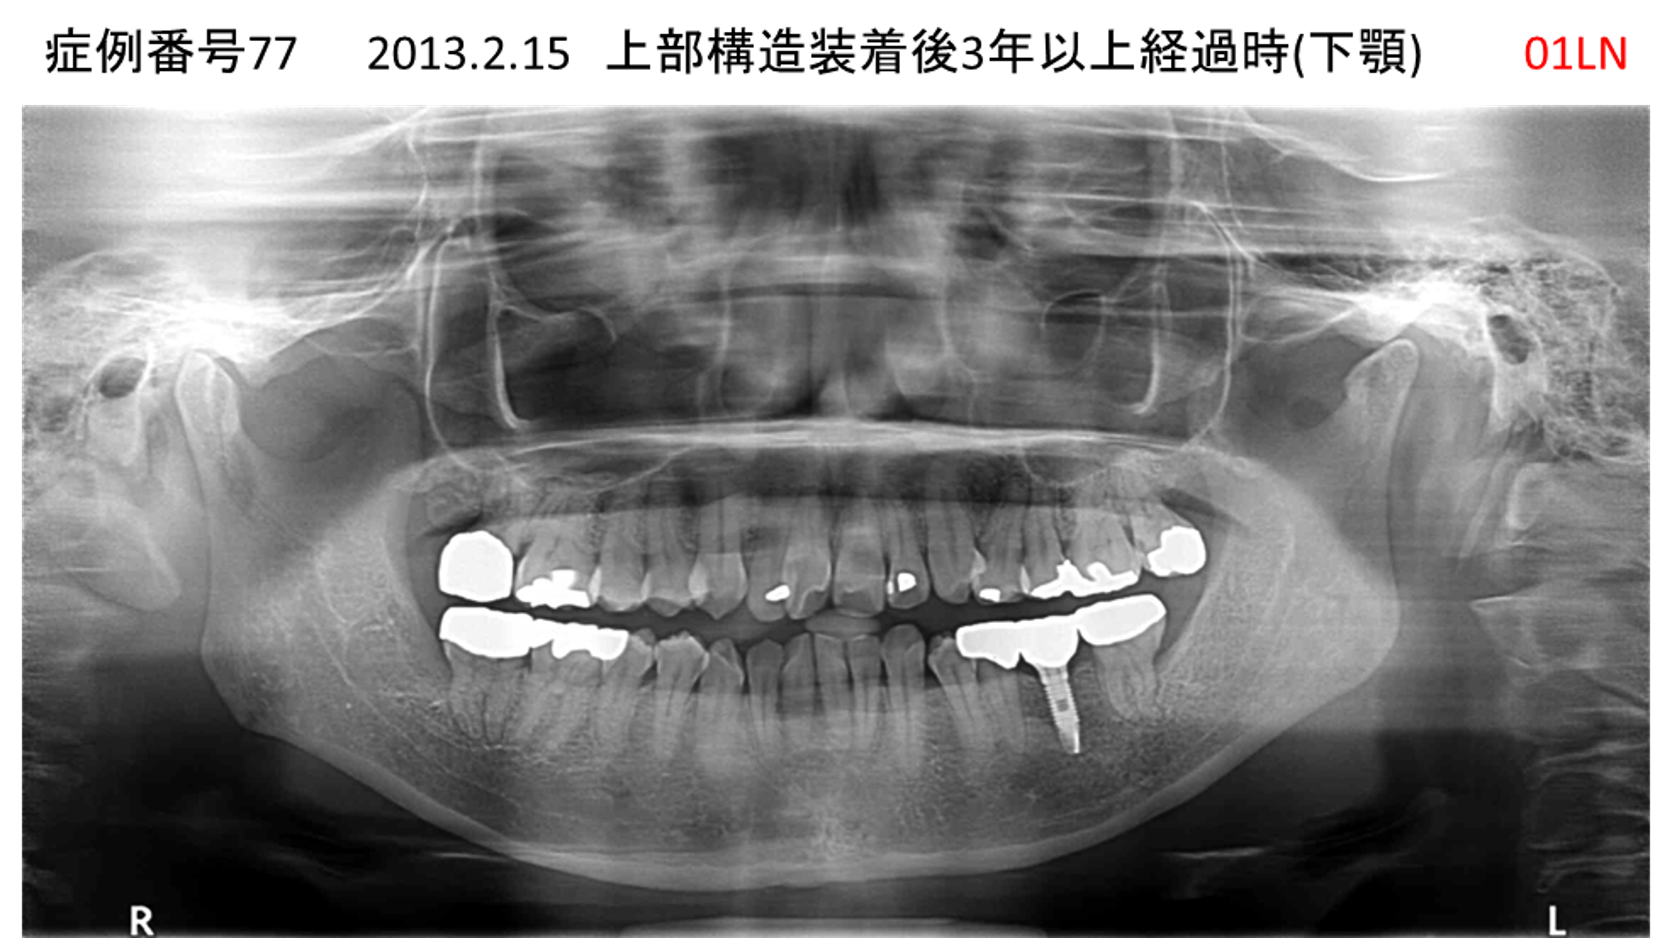

奥歯で噛めない患者様のインプラント症例

| 治療名称 |

インプラント |

| 治療費用 |

365万円+税 |

| 治療期間 |

5か月 |

| 患者さんの症状(主訴) |

奥歯で噛めない。上の前歯が揺れてきた。 |

| 治療内容 |

抜歯即時インプラント |

| 治療結果 |

食事に困らない。見た目がとても良くなった。 |

| 治療の注意点(リスク/副作用) |

インプラントが壊れたら再治療が必要 |